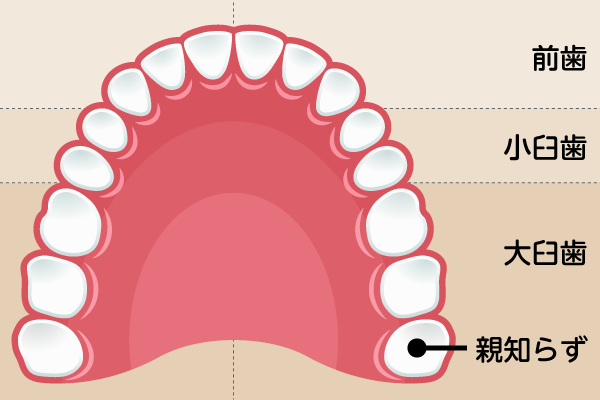

親知らずは、最も奥に生えてくる第3大臼歯です。完全に埋まっていたり、まっすぐ生えていたりして周囲の歯や歯肉に悪影響を及ぼしていない場合は、無理に抜く必要はありません。私たちは「将来のドナー(移植用)」としての価値も考慮します。将来、他の大切な奥歯を失った際に、ご自身の親知らずを移植して再利用できる可能性があるからです。目先の状況だけでなく、10年、20年先のお口の健康を見据えて、抜歯の是非を慎重に判断します。

放置が招くドミノ倒しのリスク

一方で、横向きに生えて隣の歯(7番)を圧迫している場合や、清掃性が悪くむし歯・歯周病の原因となっている場合は、現状で痛みやトラブルが起きていなくても抜歯を推奨します。放置すると、親知らずだけでなく手前の健康な歯まで共倒れになるリスクがあるからです。また、自覚症状がなくても歯並びを乱す原因になることもあります。抜歯が必要と判断した際は、歯科用CTで詳細に確認した上で、安全性を最優先に処置を行います。